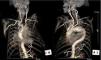

We present the case of a 76-year-old Caucasian man with a type 1 endoleak at the proximal edge of a thoracic stent-graft (Talent™ 38 mm×114 mm) detected four years after endovascular treatment of a large symptomatic saccular aneurysm in the distal aortic arch. The patient refused any interventional treatment for the endoleak and remained on medical therapy with no evolving symptoms. Surveillance cardiac tomography (CT) showed the aneurysm continuing to expand, extending towards the chest wall and causing erosion of the ribs (Figure 1).

Figure 1.

ECG-gated cardiac computed tomography of our patient showing the natural history of a left untreated type 1 endoleak (arrowhead) at the proximal edge of a stent-graft in the aortic arch (Ao). Upper panel (A1–C1) presents three-dimensional reconstructions (volume-rendering technique); lower panel (A2–C2) presents the corresponding images in the axial plane (maximum intensity projection). Over time (from A to C), the aneurysmal sac (*) continued to be pressurized and expanded towards the chest wall, ultimately causing erosion of the second left rib (box).